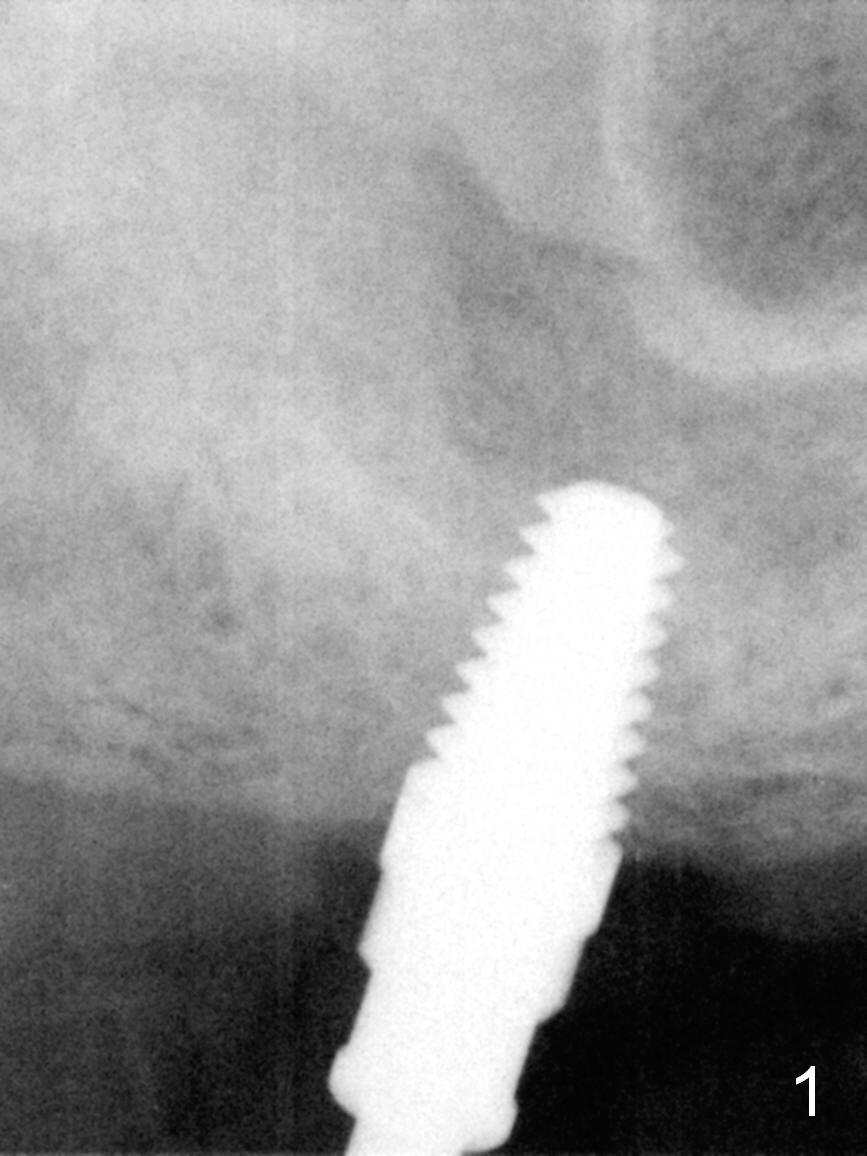

As planned, the osteotomy at #3 is underprep (using 3 mm reamer), followed by taps until 5x11 mm (Fig.1). When a 6x11 mm implant is being placed with high torque (Fig.2 (*: sinus lift)), bone mesiobuccal to the implant is starting to green-stick fracture. After flap suturing, a 5x3 mm abutment is placed and adjusted for the height. In fact the long vertical edentulous space is an artifact. An immediate provisional is fabricated with clearance (Fig.3,4). The adaptation of the provisional to the implant/abutment is so good that cement is not necessary for retention. When the wound heals, the provisional is too short to be retentive. It is not recemented. A healing screw is placed until the implant is restored.